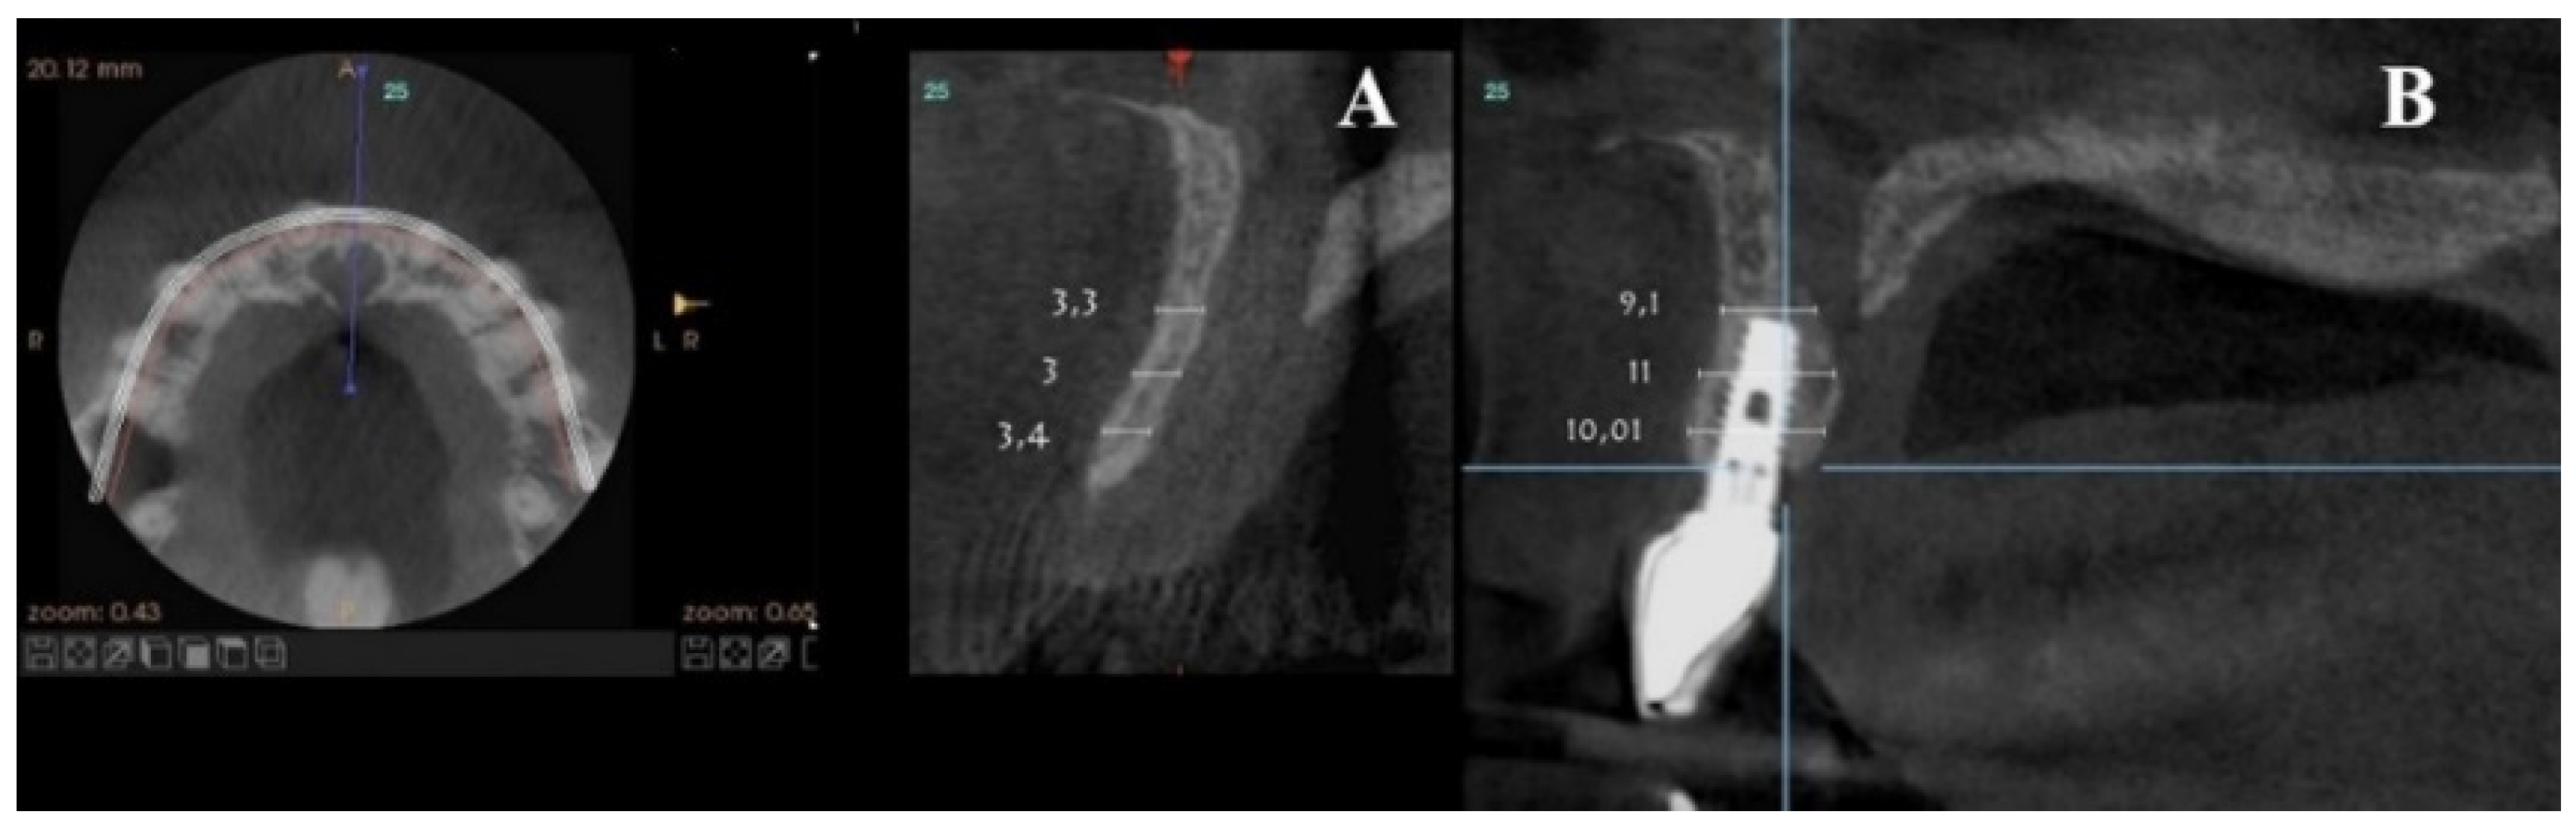

Axial sections corresponding to the middle part of the NPC showed the collapse of the vestibular plate and revealed the conduit’s size. All the cases presented thinning of the palatal ridge due to marked widening of the incisive foramen (Figure 2); so, according to the SAC Classification (i.e., simple, advanced, or complex), they were categorized as complex [2]. In addition, careful consideration had to be given to the nasopalatine bundle for correct three-dimensional positioning of the implant. Since the vertical and horizontal defects demanded bone augmentation before implant placement [17], a diagnostic wax-up was performed to determine the amount of bone needed in each case.

Figure 2.

Representative sections of a Cone Beam Computed Tomography (CBCT) scan in which the bone thickness of the maxillofacial region and the widening of the incisive foramen are observed. (A) Occlusal view. (B) Sagittal view.

For each patient, pre- and post-treatment CBCT measurements of the anterior ridge thickness of the aforementioned foramen were taken at different heights, i.e., 4, 8, and 14 mm apical to the marginal bone ridge. CBTC was performed at 90 Kv and 10 mA, with an 18-second exposure cycle on a Promax-3D plus equipment (Planmeca, Finland). The obtained images were analyzed with Romexis 4.4.0.R. A field of view of 40 mm by 50 mm was used, with an isoropic voxel size of 75 µm (0.075 mm). Serial slices (0.5 mm in thickness) with 0.5 mm reconstruction intervals were analyzed.

For each patient, pre-surgical measurements were taken in the vestibular table observed from the sagittal plane, from the vestibular cortex to the anterior cortical wall of the NPC. In the same fashion, the vestibulo–palatine width was measured between 6.5 and 9.5 months (7 months on average) after implant activation.

Pre-surgical vestibulo–palatine width (mean ± standard deviation) of the anterior ridge at different heights (4, 8, and 14 mm apical to the marginal bone ridge) was 3.5 ± 2.0 mm; 5.4 ± 1.5 mm, and 6.1 ± 1.9 mm, respectively. Post-treatment total vestibulo–palatine width was 10.1 ± 2.0 mm, 10.5 ± 1 mm, and 13.4 ± 3.0 mm, respectively (Table 4).